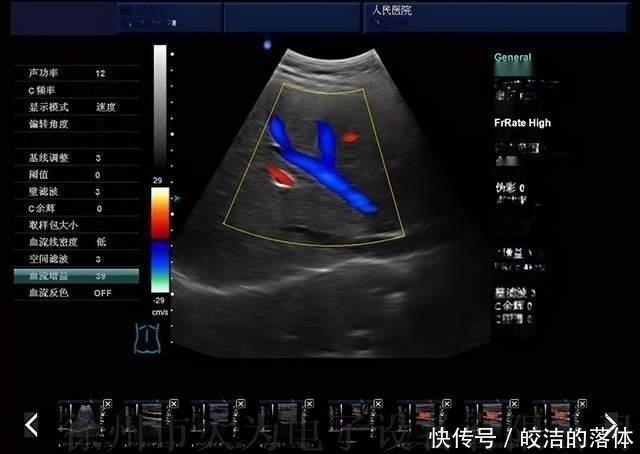

多普勒彩超一般的B超都是二维平面,三维B超可以在多个角度的回波信号处理成立体图像,这个原理就像激光扫描3D成像一样。